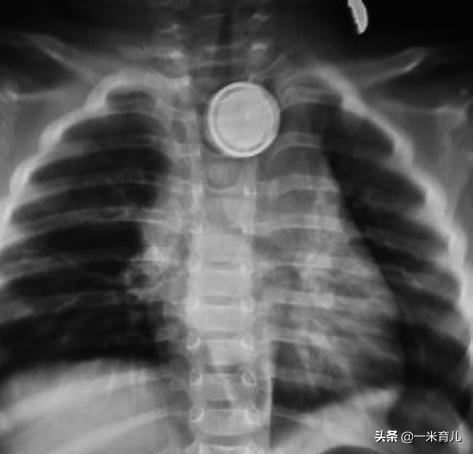

阿芮家5岁女儿把阿芮的耳钉吃了!看着既不敢大声哭、又不敢咽唾沫的女儿,阿芮急得像热锅上的蚂蚁,赶紧把女儿送到医院,幸亏医生在食道镜下把耳钉取了出来。

阿芮女儿吞食耳钉

儿童吞食的常见物品中,硬币是最常保留在食管中的异物。

在儿童消化道异物中,70%~75%的消化道异物发生在食管,以食管入口处最多见。

男孩吞食硬币